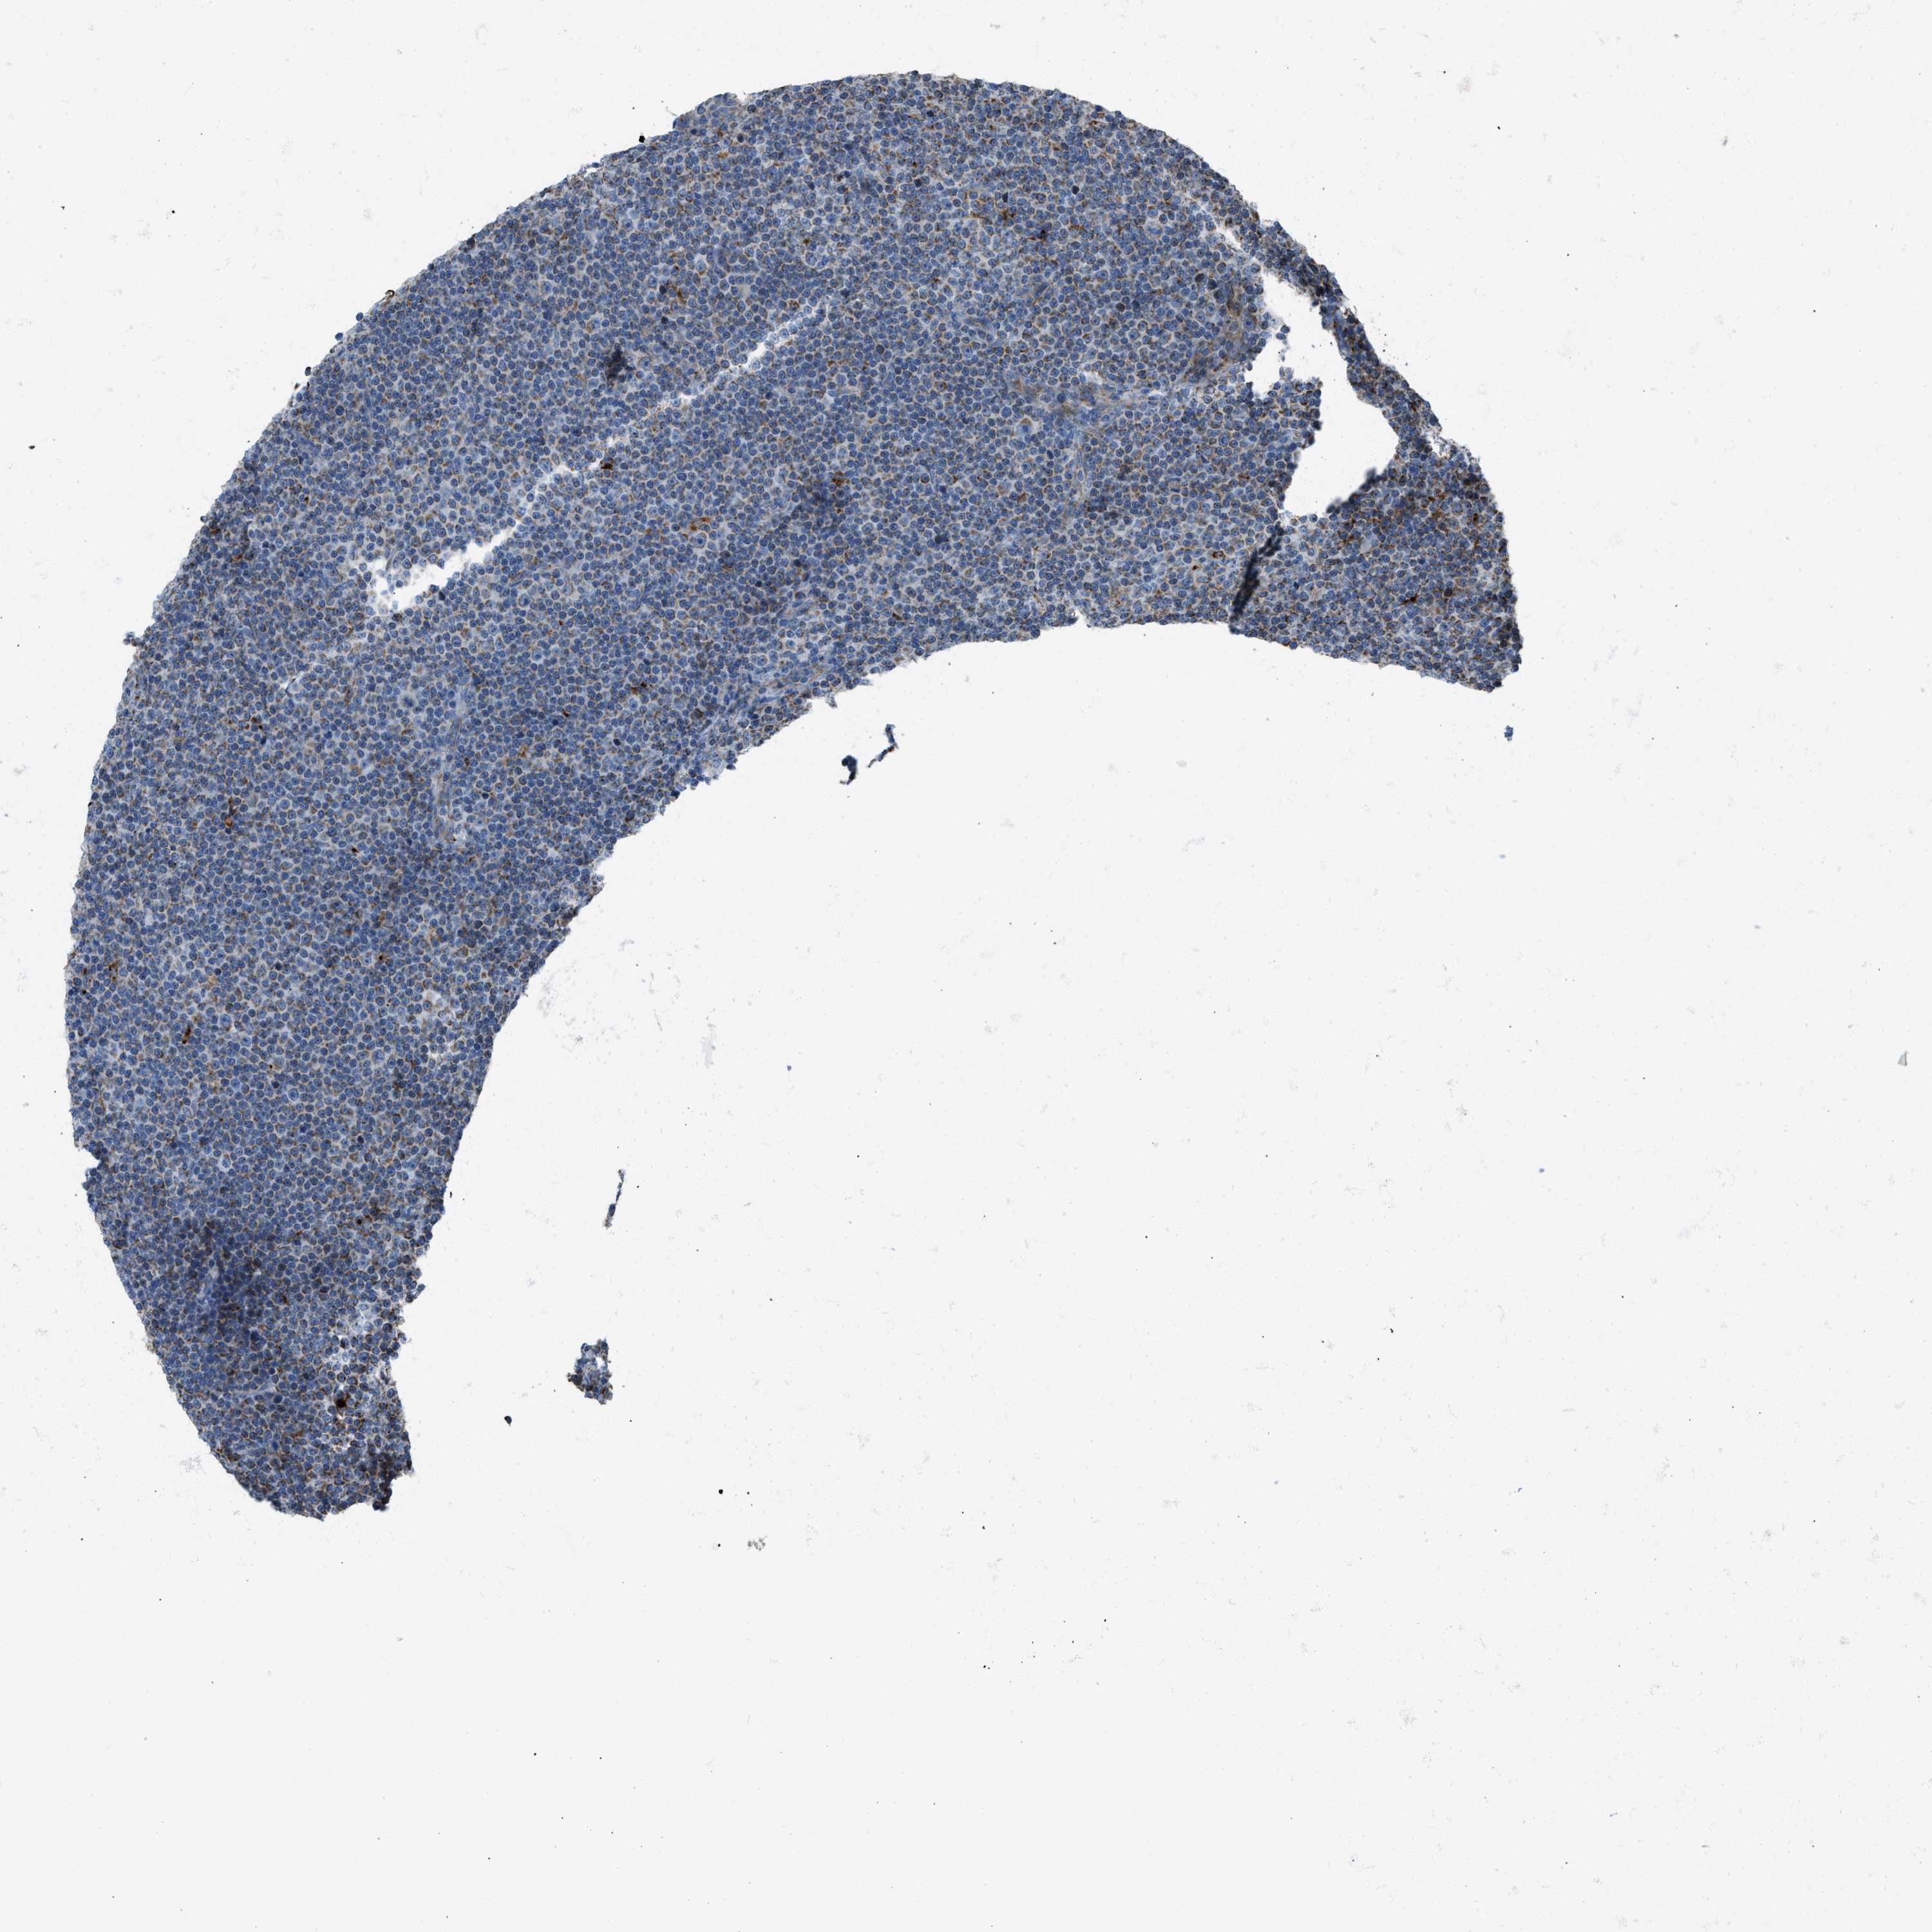

LYMPHOMA - Protein expressioni

A mouse-over function shows sample information and annotation data. Click on an image to view it in a full screen mode. Samples can be filtered based on level of antibody staining by selecting one or several of the following categories: high, medium, low and not detected. The assay and annotation is described here.

Antibody stainingi

Antibody staining in the annotated cell types in the current human tissue is reported as not detected, low, medium, or high, based on conventional immunohistochemistry profiling in selected tissues. This score is based on the combination of the staining intensity and fraction of stained cells.

Each image is clickable and will lead to virtual microscopy that enables deeper exploration of all samples and also displays staining intensity scores, fraction scores and subcellular localization as well as patient and tissue information for each sample.

Antibody HPA016552

Staining

High

Medium

Low

Not detected

Intensity

Strong

Moderate

Weak

Negative

Quantity

>75%

75%-25%

<25%

None

Location

Nuclear

Cytoplasmic/membranous

Cytoplasmic/membranous,nuclear

Hodgkin's disease, NOS

Malignant lymphoma, non-Hodgkin's type, High grade

Malignant lymphoma, non-Hodgkin's type, Low grade